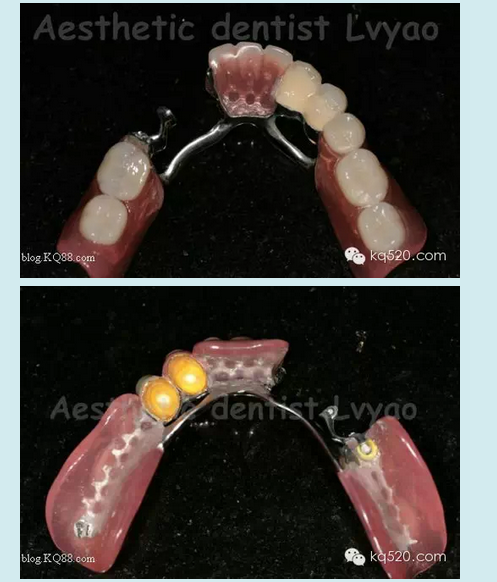

本病例在去年完成,患者是我的親人,現(xiàn)在修復(fù)體用的很好很舒適。患者上頜牙良好,下頜余留牙左下345良好,右下34有不同程度的牙槽骨吸收,右4松動(dòng)2度、右3松動(dòng)1度,臨床冠根比失調(diào)。原患者使用普通支架活動(dòng)義齒,現(xiàn)因基牙問題等因素導(dǎo)致使用不佳,以保存基牙的原則等因素,本人設(shè)計(jì)了套筒冠與栓體栓道式附著體聯(lián)合應(yīng)用的修復(fù)技術(shù)。有關(guān)文獻(xiàn)報(bào)道,對(duì)于患者牙列缺損 少量基牙伴牙槽骨吸收或牙周病,不宜固定修復(fù)又對(duì)美觀、功能、舒適要求高??刹捎锰淄补谂c栓體栓道式附著體修復(fù)技術(shù)聯(lián)合的方法,此方法充分利用了栓體栓道式附著體固位力強(qiáng),義齒清洗時(shí)仍可維持垂直距離以及其固位體隱蔽和套筒冠技術(shù)的良好的基牙保護(hù)性能及可以在垂直及水平方向都能提高義齒的固位和穩(wěn)定性等優(yōu)點(diǎn)。有學(xué)者研究調(diào)查,發(fā)現(xiàn)套筒冠與栓體栓道式附著體聯(lián)合應(yīng)用的修復(fù)技術(shù)具有美觀、舒適、固位穩(wěn)定性良好、咀嚼效率高、保存保護(hù)基牙等優(yōu)點(diǎn)。實(shí)驗(yàn)表明牙周病患者能較快地適應(yīng)套筒冠義齒,咀嚼功能有所提高;套筒冠義齒具有良好的夾板固定效果,顯著降低牙周病患牙的松動(dòng)度,顯著減小牙周病患牙的牙周袋深度。

此病例正是如此,套筒冠主要的作用是保存維持了嚴(yán)重牙槽骨吸收的右下34基牙,改善了原基牙的臨床冠根比,縮短臨床冠高度大大減輕了對(duì)基牙承受的牙合力等其他應(yīng)力,減緩了牙槽骨的吸收,維持了基牙的使用壽命,再利用栓體栓道式附著體幫助,應(yīng)力分布更為均勻,從而修復(fù)后達(dá)到了非常好的效果。說了那么多,還是看看病例照片吧:

有關(guān)修復(fù)體細(xì)節(jié)影像

套筒金沉積外冠效果更佳